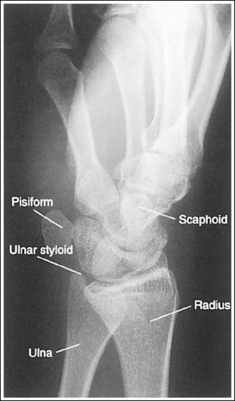

Wrist: Posteroanterior Projection

See Figure 4-29 and Box 4-11.

Contrast and density are adequate to demonstrate the scaphoid fat stripe.

• Significance of the scaphoid fat stripe. The scaphoid fat stripe is one of the soft tissue structures that should be visible on all PA wrist projections (Figure 4-30). It is convex and located just lateral to the scaphoid in an uninjured wrist. A change in the convexity of this stripe may indicate to the reviewer the presence of joint effusion or of a radial side fracture of the scaphoid, radial styloid process, or proximal first metacarpal.

The wrist is positioned in a PA projection. The radial and ulnar styloids are at the extreme lateral and medial edges, respectively, of each bone. The radioulnar articulation is open, and superimposition of the metacarpal bases is limited.

• Rotation of the wrist and forearm is controlled by the position of the hand, elbow, and humerus. A PA projection is accomplished by abducting the humerus until it is positioned parallel with the IR and the elbow is in a lateral projection. The hand is then pronated, placing the wrist in a PA projection (Figure 4-31).